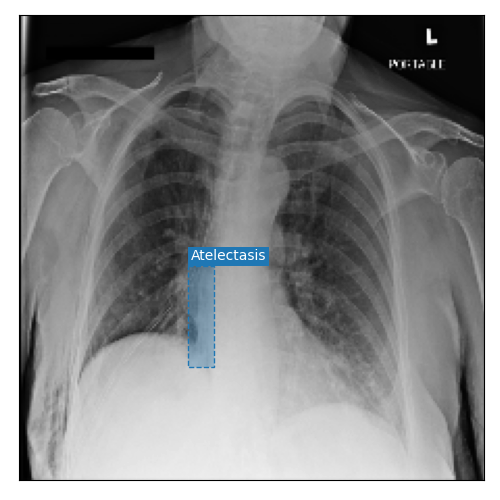

Qualitative Results

As shown in Fig. 4 Loc-ADPD detects cardiomegaly almost perfectly, as it is always exactly localized at one anatomical region. Other pathologies are detected but often with too large or too small boxes as they only cover parts of anatomical regions or stretch over several of them, which cannot be completely corrected using WBF. Detection also works well for predicting several overlapping pathologies. For qualitative comparisons between Loc-ADPD and MIL-ADPD, we refer to Appendix 0.B.